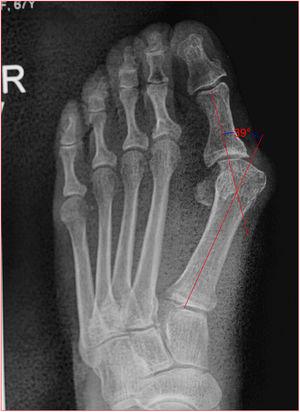

Desviación lateral del eje de alineación metatarso-falángico de 1er dedo.

Ángulo del Hallux 34° (VN <15°).

MEDIDAS RADIOGRAFICAS El Ángulo del Hallux Valgus (HVA) se forma por la intersección de los ejes longitudinales de la falange proximal y el primer metatarsiano. Un HVA es considerado normal si es menos de 15 grados.

Angulo de valgo: es la intersección del ejes longitudinales del primer metatarsiano y de la falange proximal del hallux. Normal hasta 15 grados